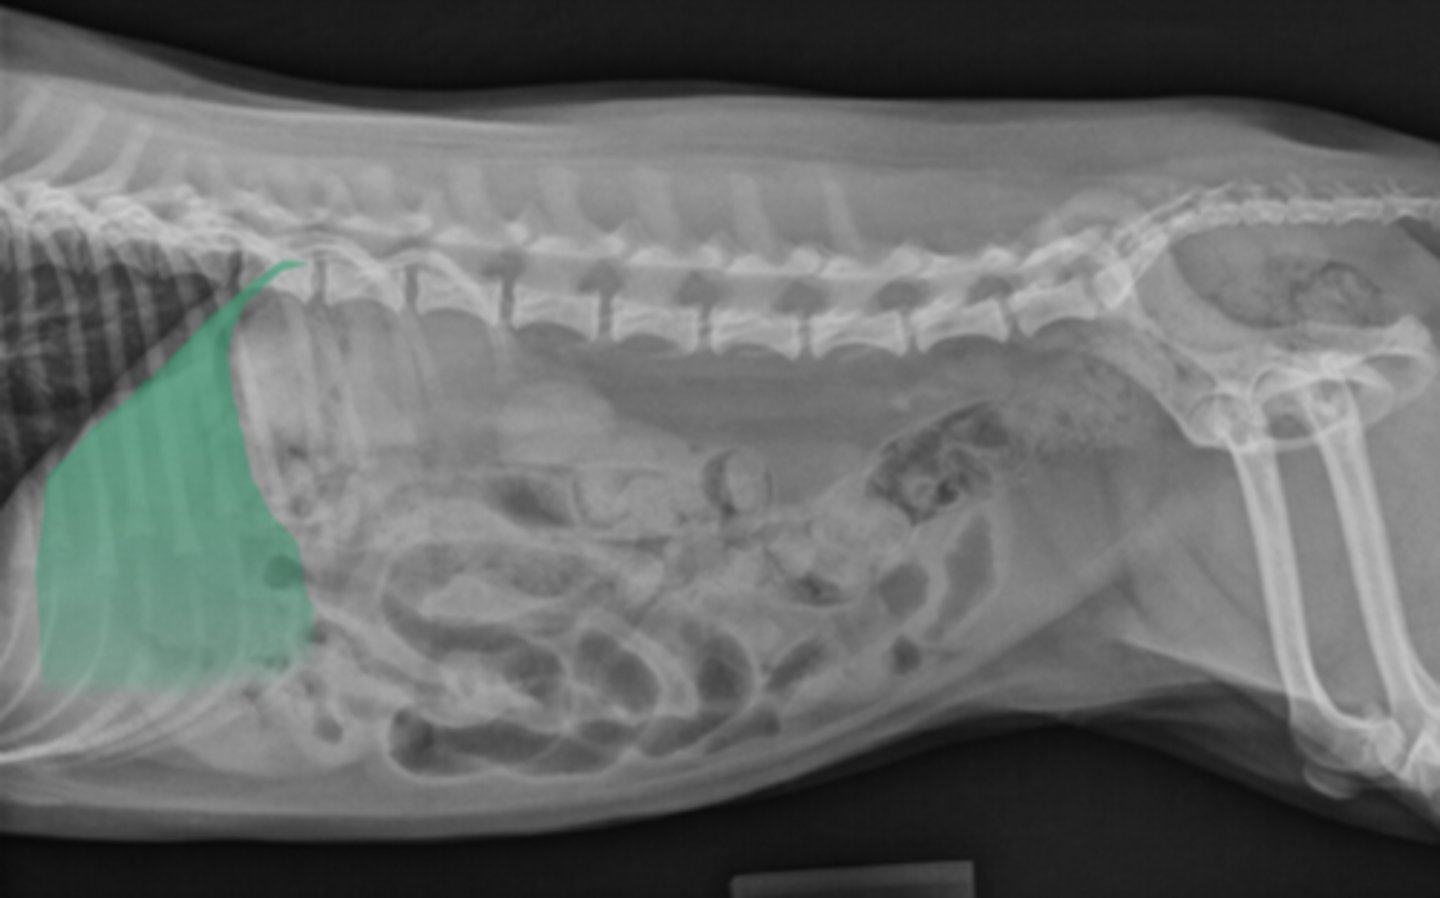

Radiograph; can't see much in abdomen - why?

What are these opacities on the cat?

What organ is this?

Hepatomegaly

What is an enlarged liver called?